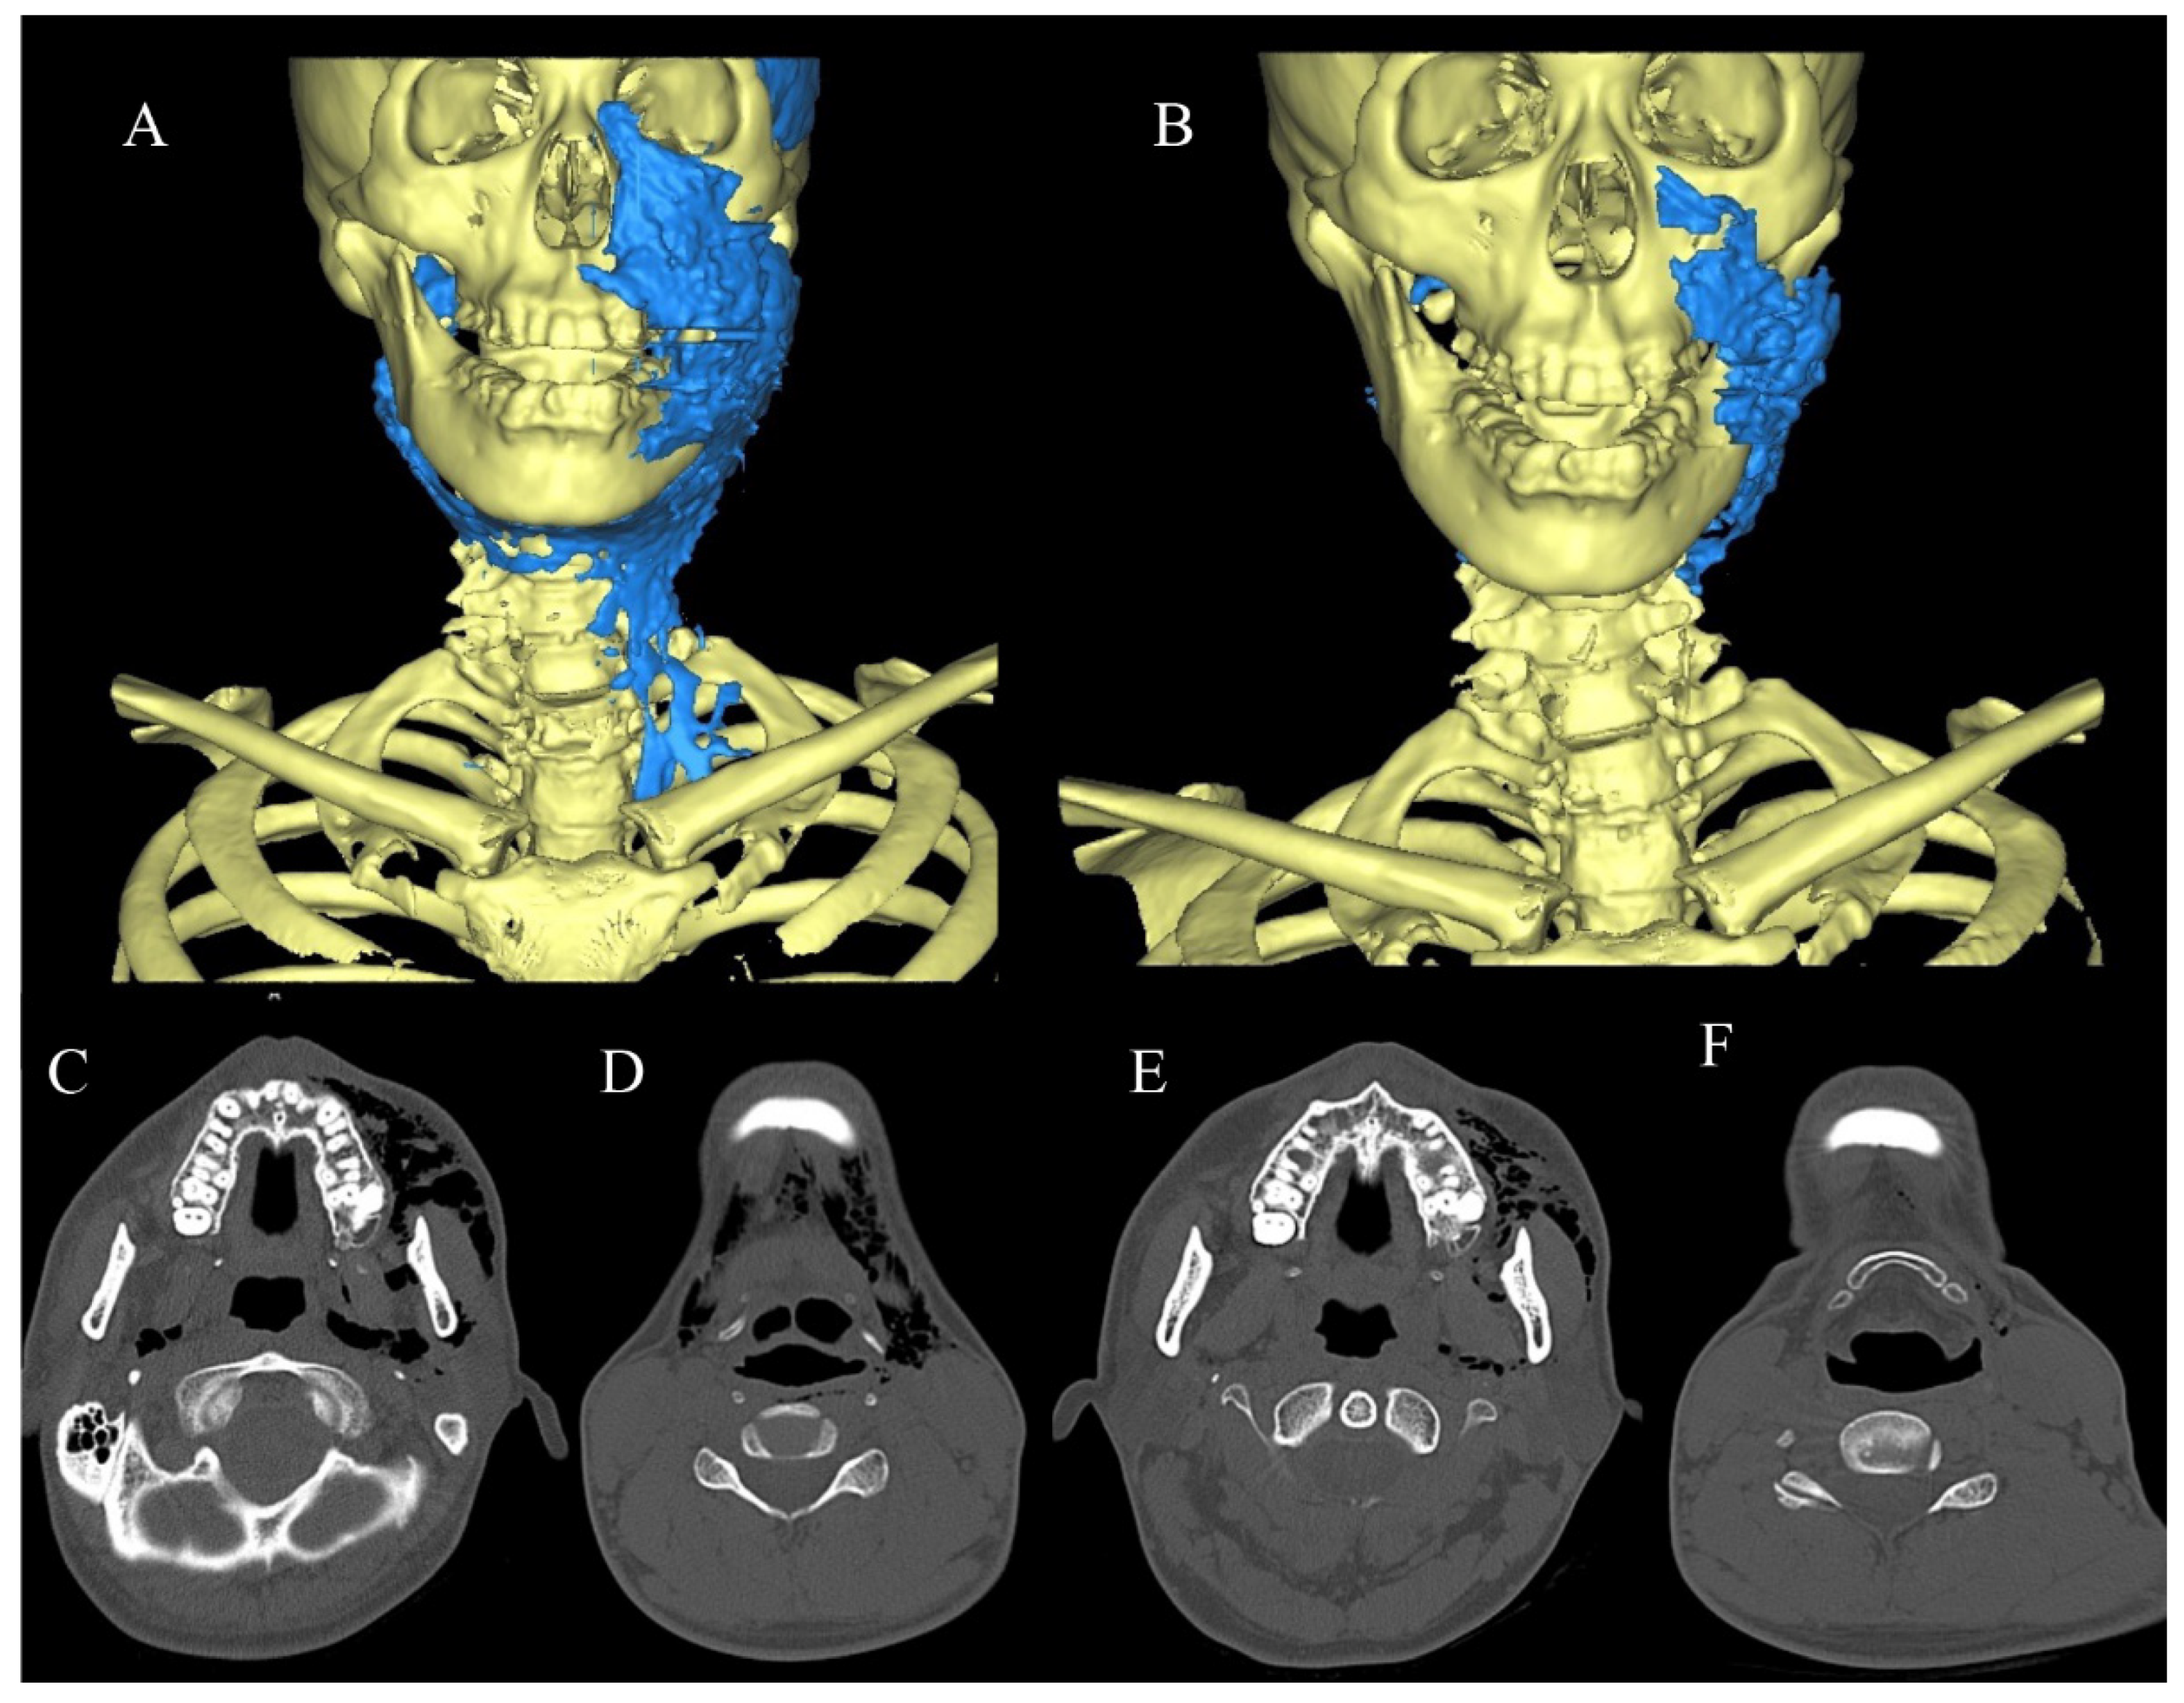

2.3.2. Case 2

2.3.3. Case 3